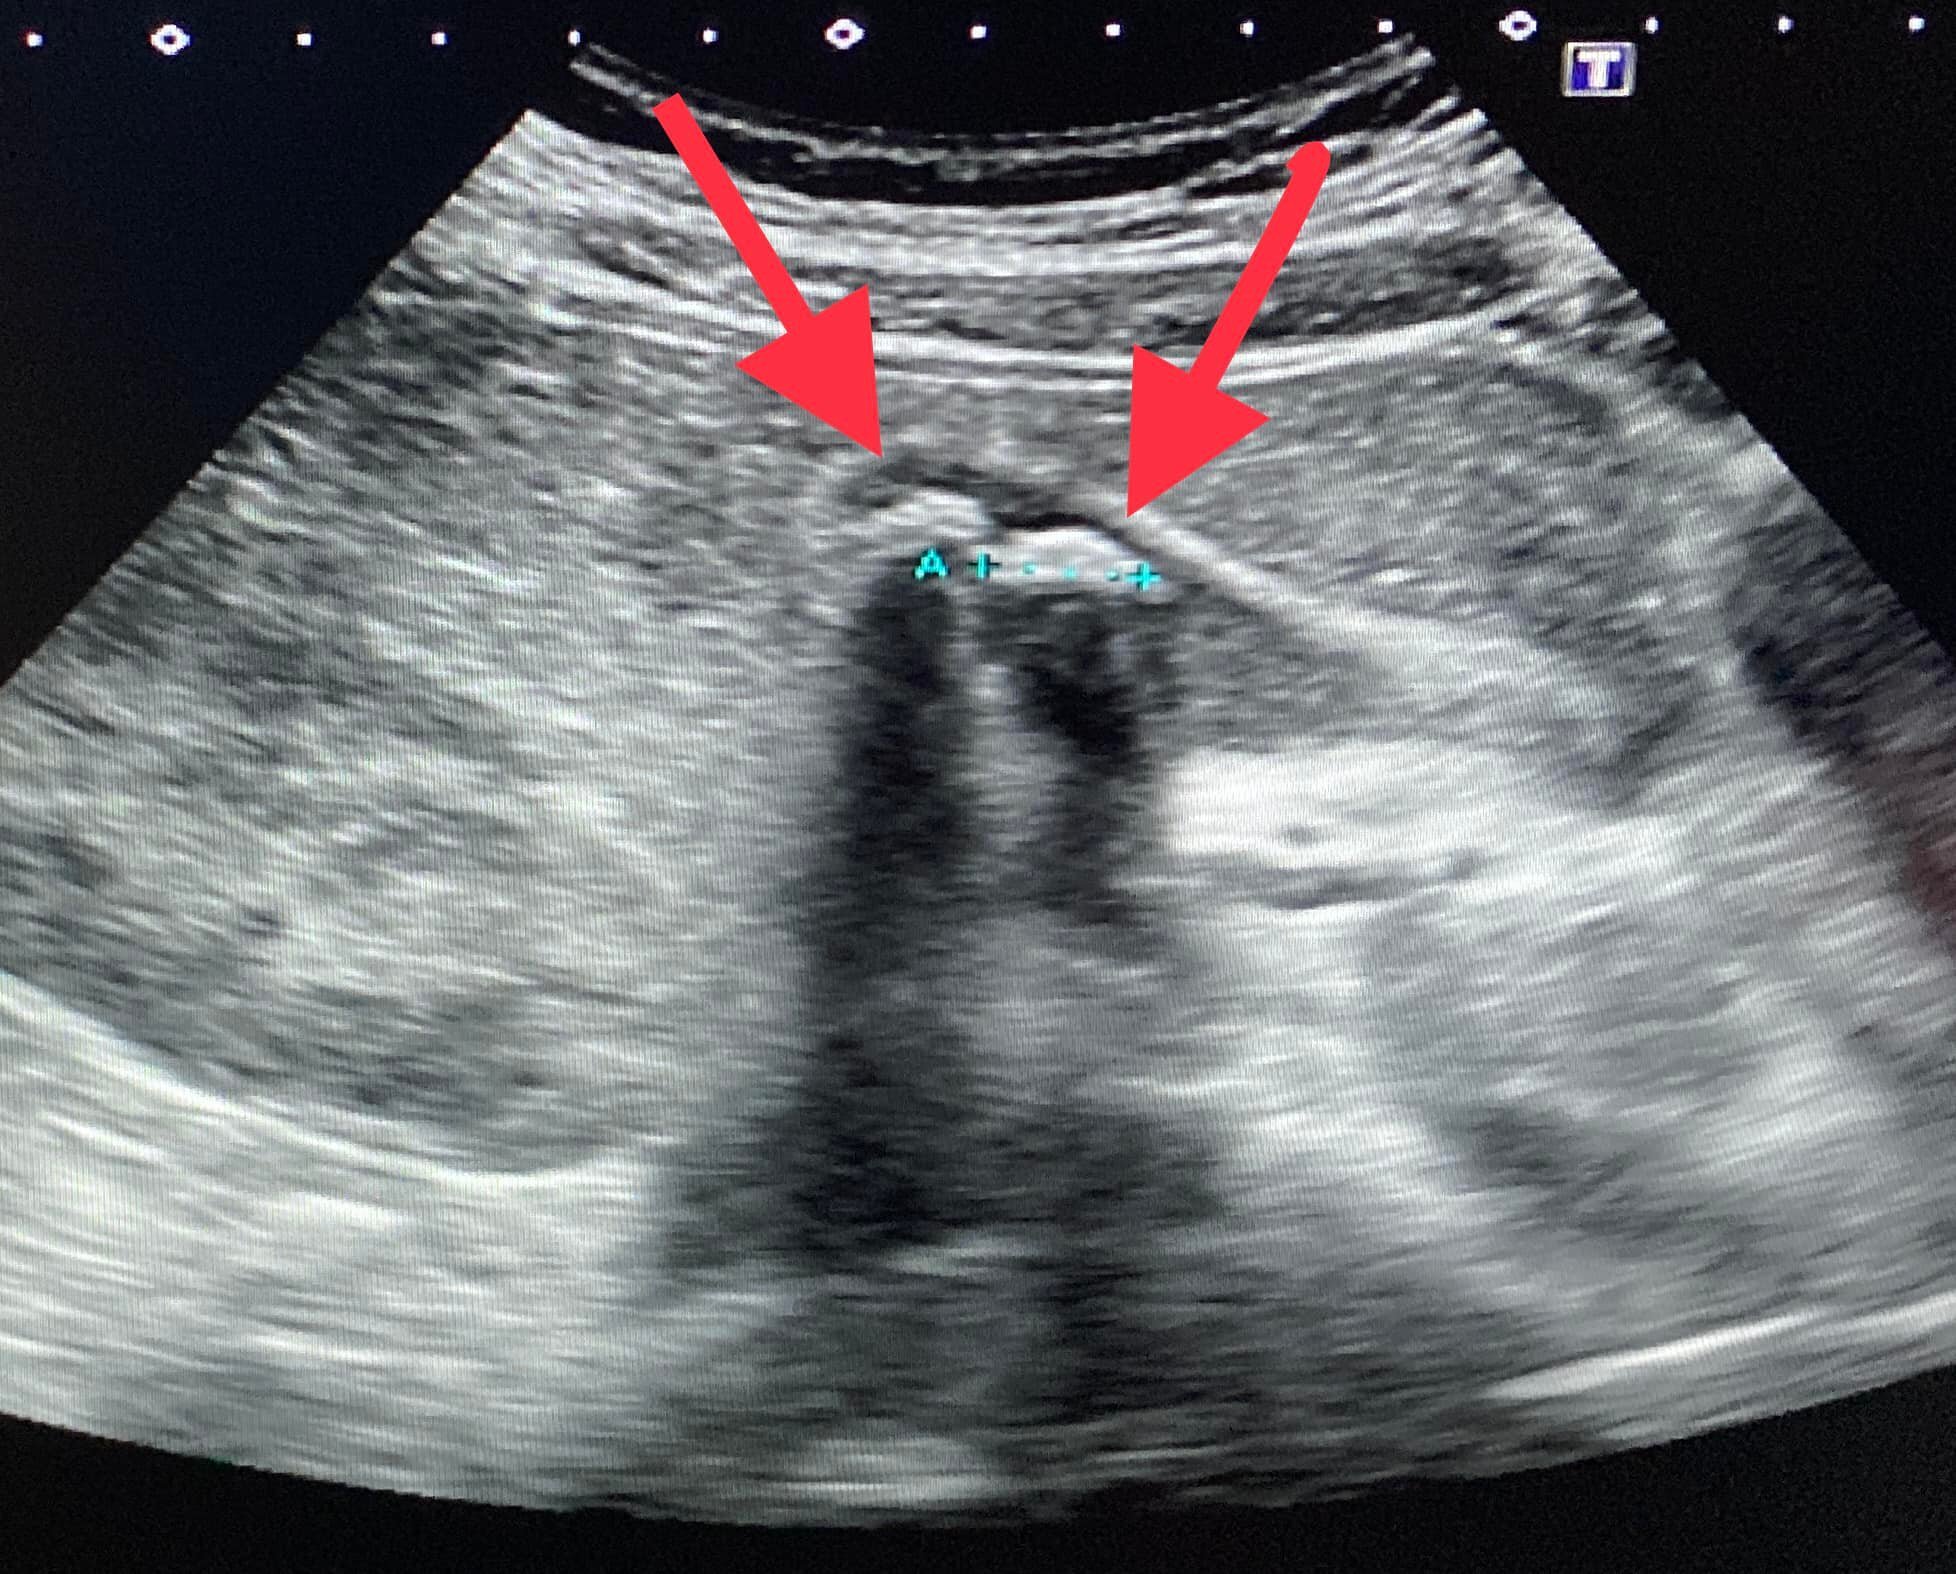

錢政弘推斷,這可能是膽結石引起的疼痛,經超聲波檢查,結果發現該男生的膽囊佈滿膽泥、已經沒有正常的膽汁,且至少有五顆直徑1.2厘米以上的膽結石漂浮其中。錢政弘大感驚訝,他說:「我是常見到膽結石的病患,不過這位年輕人才17歲耶!他的結石這麼多,應該前幾年就有了。」